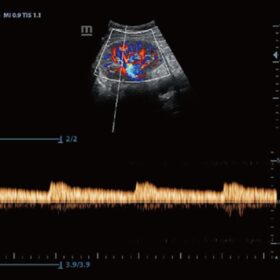

Ultrasound Mindray Z60 – Image Gallery